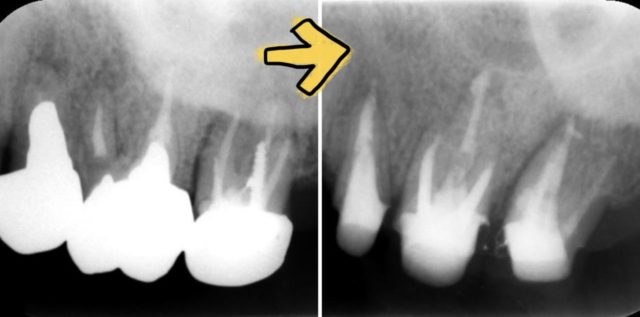

左上7番はデンタルX線画像で垂直性の骨吸収が見られる為、歯が破折している場合はインプラントの計画で治療介入をしました。

幸い破折していなかったので感染根管治療をしました。

左上5、6、7番は全て神経が無い歯ですが、当院では根管内洗浄から歯の土台を立ててオールセラミックスを入れるまで、全工程をしっかり丁寧に再治療します。

無事根尖まで綺麗に感染除去できました。